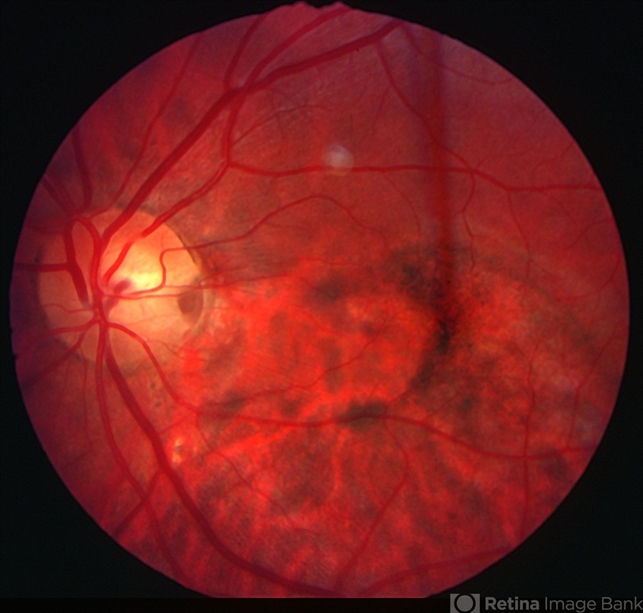

- Optic disc pit

- optic disc pit, congenital optic nerve pit

- Optic disc pit - R stereo. Note chronic RPE changes from subretinal fluid